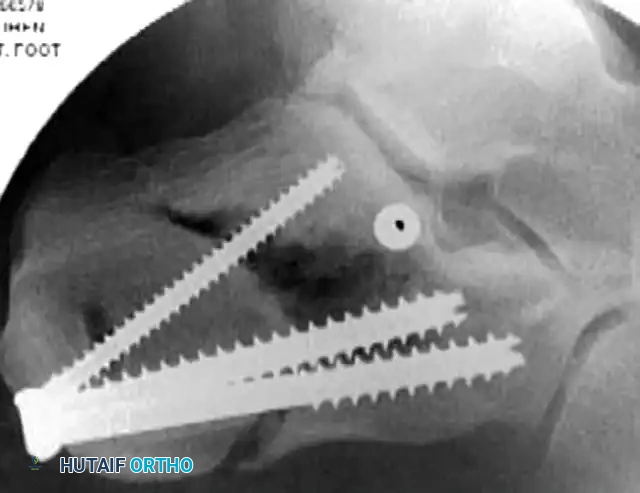

- Place 3.5-mm or 4.0-mm partially threaded cortical screws over the provisional K-wires. These screws are directed from lateral to medial, compressing the lateral articular fragment against the medial sustentacular fragment.

- To maintain the corrected position of the tuberosity, insert fully threaded screws from the posterior tuberosity directed anteriorly toward the calcaneocuboid joint, parallel to the initial Steinmann pin. Fully threaded screws are preferred here to act as position screws, preventing loss of calcaneal length.

- Perform a final fluoroscopic check to confirm extra-articular hardware placement, restoration of Böhler’s angle, and correction of varus alignment.